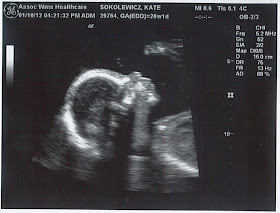

Here are some ultrasound pictures from our 20-week check-up:

Great picture of Baby Soko with his toes touching his forehead

Baby Soko face!

Proof that it's a boy!

"Hi mom & dad!"

Amazing profile shot of our beautiful SON!